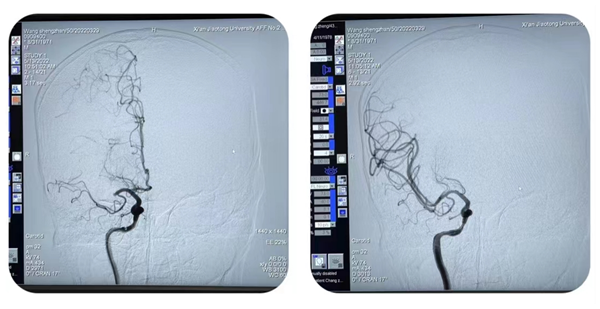

手术展播中,一例急诊取栓患者打破了原本的日程安排。一例50岁男性患者突发言语不利伴左侧肢体无力6小时入院,我院脑卒中绿色通道紧急启动,张桂莲主任紧急联系会务组,更改直播进程,对该例急诊手术进行了全国直播,手术由张茹副主任团队实施,最终手术实现了“一把通”,从患者入院至手术再通(包含急诊评估、住院流程办理、多模影像学检查等)仅耗时67分钟。急诊手术因其多种不确定性从来不是直播的常客,特别是在全国手术直播中更是极为罕见,科室打破常规思维,勇于挑战,衔接有序的卒中绿道、快速有序的手术过程、良好的手术效果令广大专家教授及介入同道纷纷称赞,为全国卒中中心及卒中绿色同道的建设展示了一个优秀的团队标杆。

图片2_副本.png

图片3_副本.png